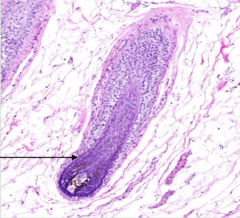

outer root sheath

Front

what is the name of this portion of the hair follicle?

Back